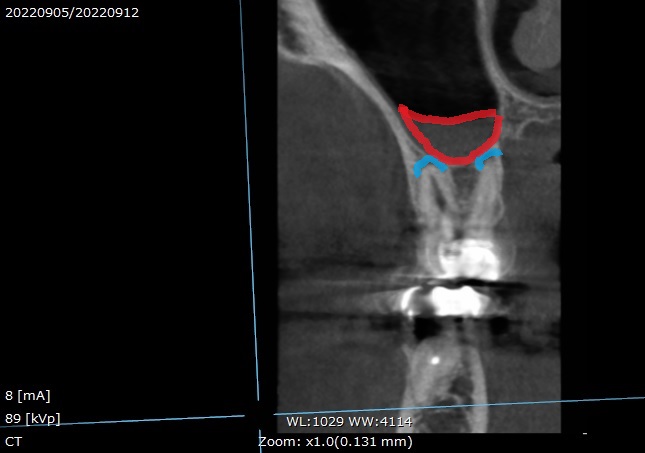

歯根の先に膿がたまった歯茎の腫れ⇒マイクロスコープ再根管治療で溶けた骨を再生